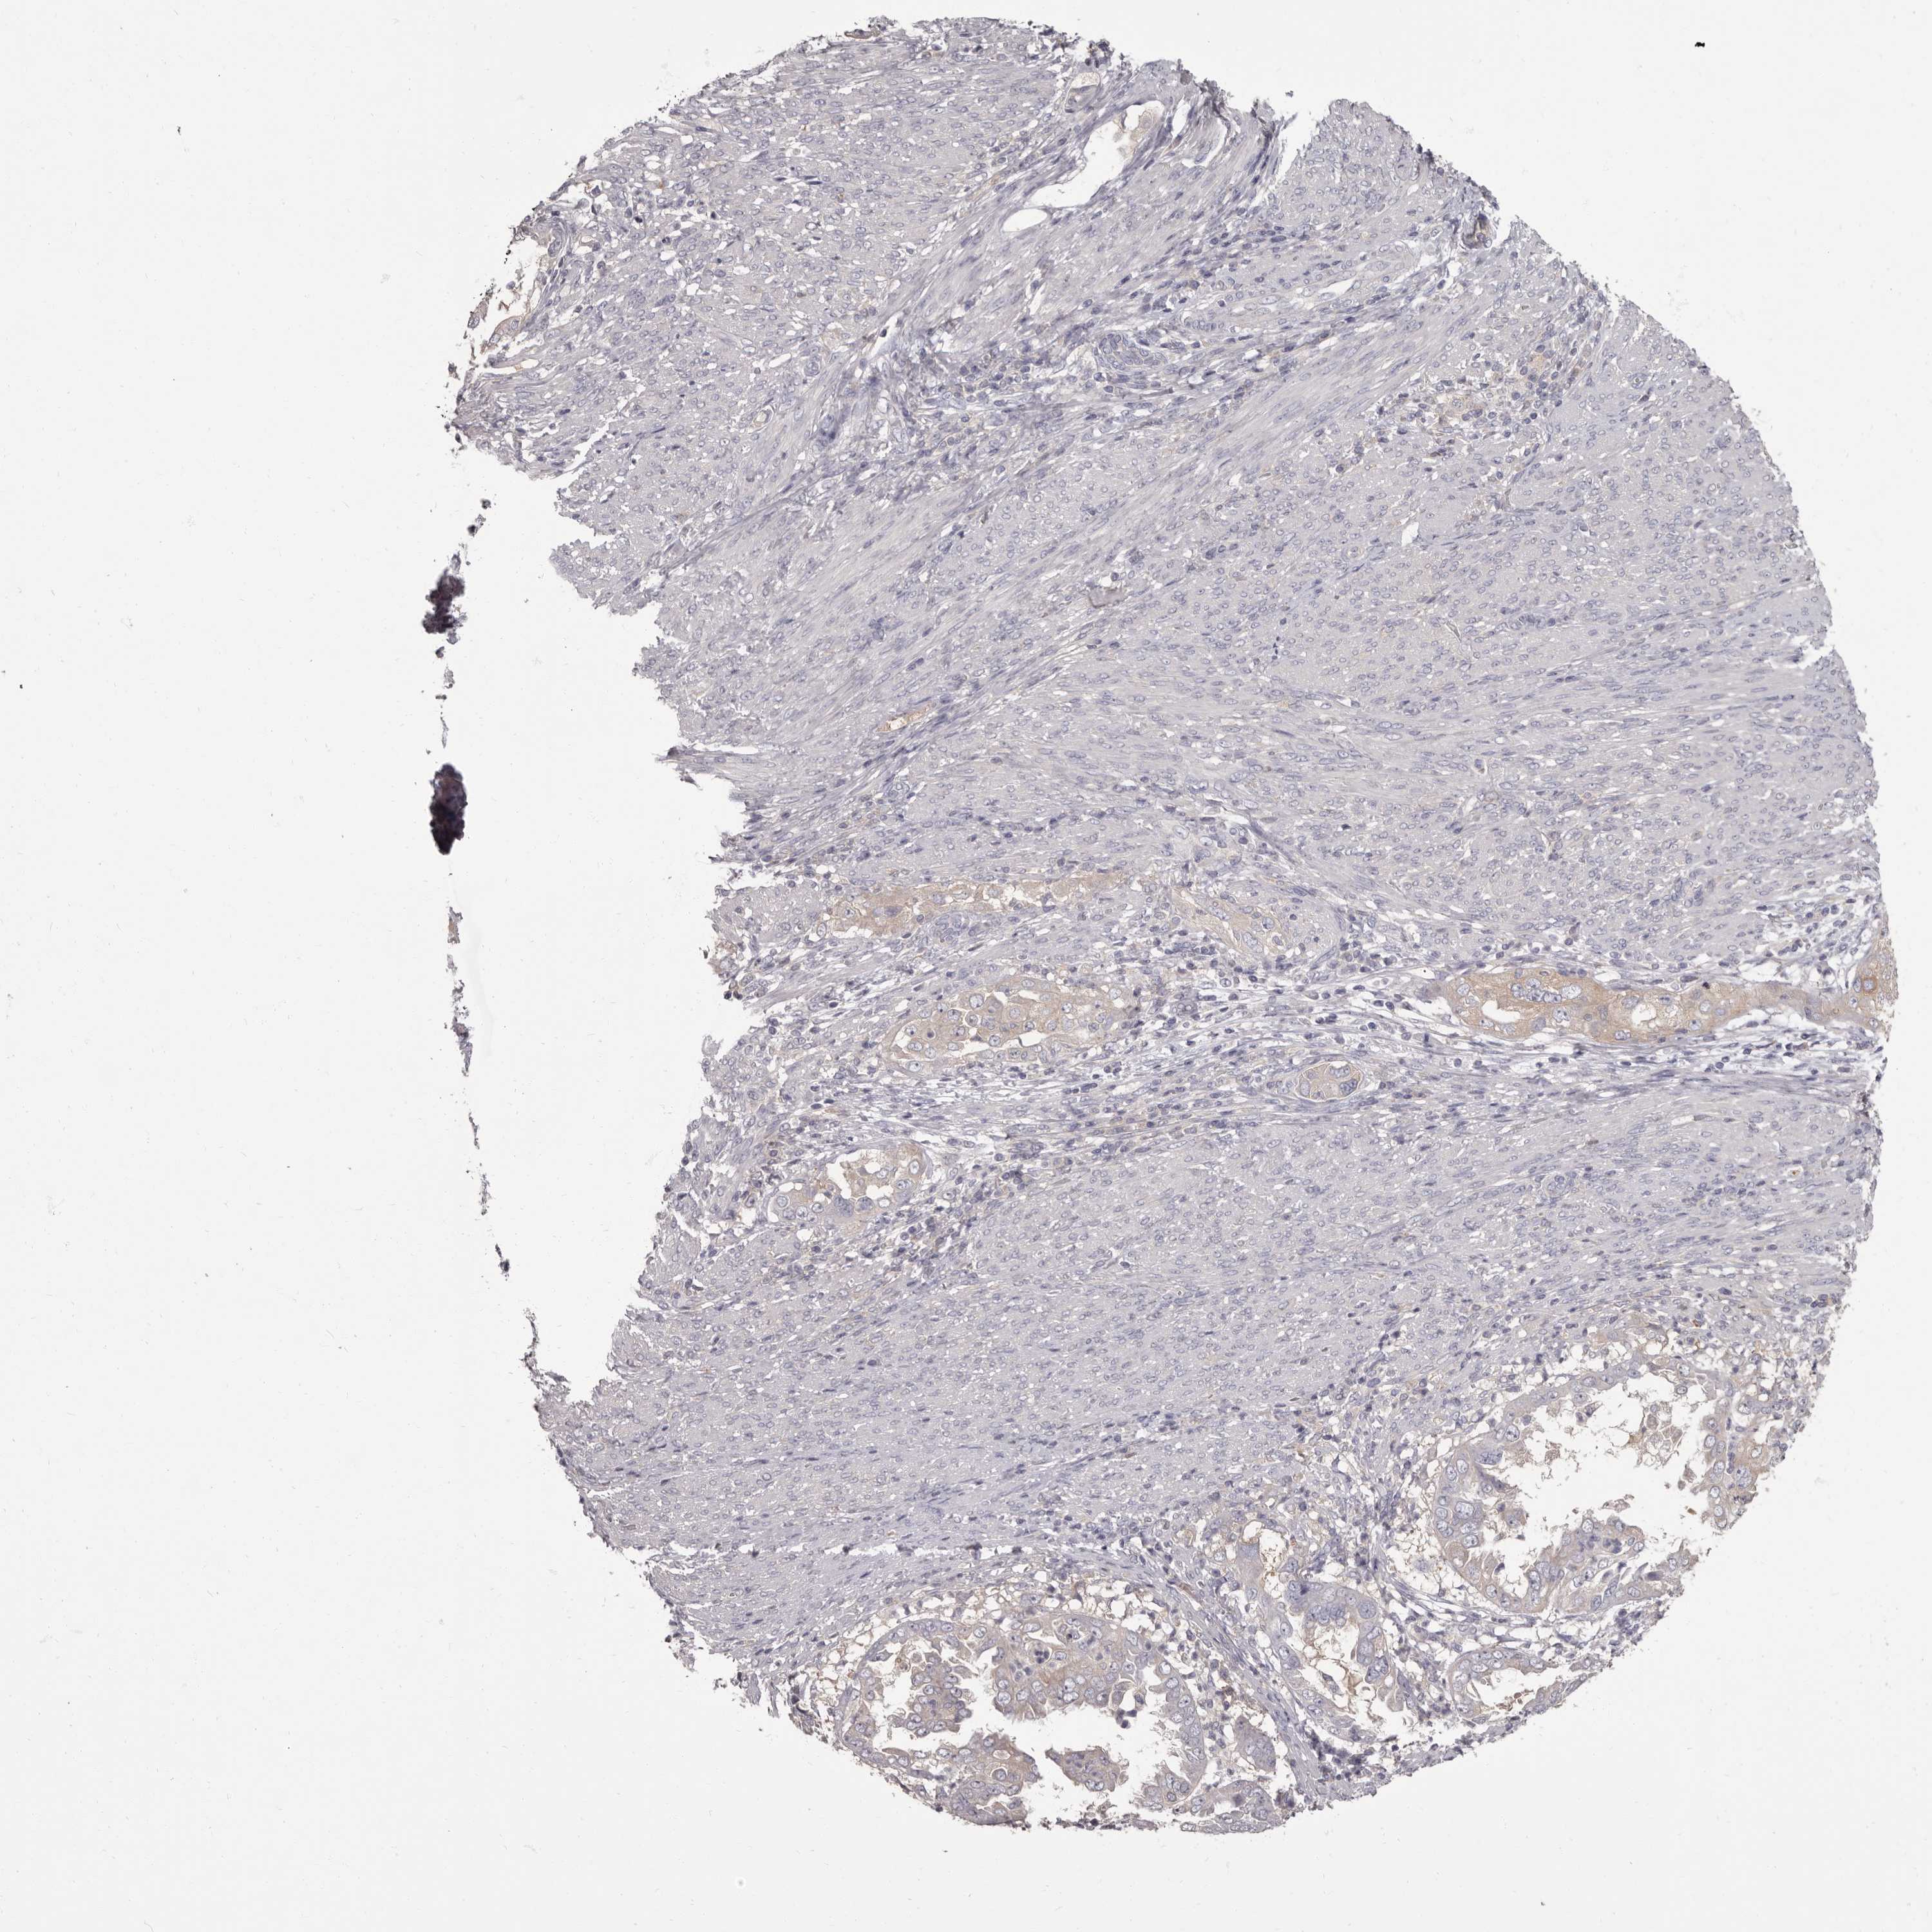

ENDOMETRIAL CANCER - Protein expressioni

A mouse-over function shows sample information and annotation data. Click on an image to view it in a full screen mode. Samples can be filtered based on level of antibody staining by selecting one or several of the following categories: high, medium, low and not detected. The assay and annotation is described here.

Note that samples used for immunohistochemistry by the Human Protein Atlas do not correspond to samples in the TCGA dataset.

Antibody stainingi

Antibody staining in the annotated cell types in the current human tissue is reported as not detected, low, medium, or high, based on conventional immunohistochemistry profiling in selected tissues. This score is based on the combination of the staining intensity and fraction of stained cells.

Each image is clickable and will lead to virtual microscopy that enables deeper exploration of all samples and also displays staining intensity scores, fraction scores and subcellular localization as well as patient and tissue information for each sample.

Antibody HPA029700

Antibody HPA029701

Antibody HPA029702

Antibody HPA029703

Staining

High

Medium

Low

Not detected

Intensity

Strong

Moderate

Weak

Negative

Quantity

>75%

75%-25%

<25%

None

Location

Nuclear

Cytoplasmic/membranous

Cytoplasmic/membranous,nuclear

Adenocarcinoma, NOS

Adenocarcinoma, metastatic, NOS